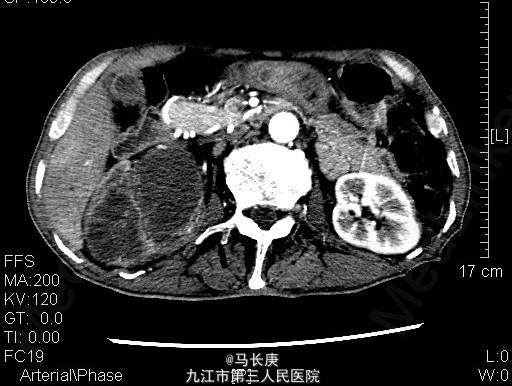

1、右上腹痛伴全程肉眼淡红血尿2月 2、患者于2月前无诱因出现右上腹痛伴全程肉眼淡红血尿,可以自行缓解,无血块、血条,无尿频、尿急、尿痛,无排尿困难,当时未引起重视,未去就医,7天前右上腹痛及血尿加重,于当地人民医院就诊,诊断为:右肾占位,现为进一步诊治于来我科进一步治疗。起病以来,一般情况尚可,近期体重明显下降。

3、查体:无明显异常 4、辅助检查:当地人民医院泌尿系CT平扫+增强:1.右侧输尿管结石2.右肾占位?(未见报告),我科fish(+)CTU:肾盂癌,侵蚀右肾包膜,左肾囊肿,慢性胆囊炎。双肾核素扫描:右肾GFR:9.5,左肾48.5

5、考虑右肾盂癌 6、入院后给予双肾核素扫描、CTU检查,考虑右肾盂癌,给予抗炎、补液、治疗。现病情平稳。 术前诊断:右肾盂癌、胆囊炎、左肾囊肿、右侧输尿管结石、贫血、低蛋白血症、胆囊炎,后行右肾癌根治术,手术顺利,术后恢复较好,术后病理示:肾恶性肿瘤(高分化肉瘤)。